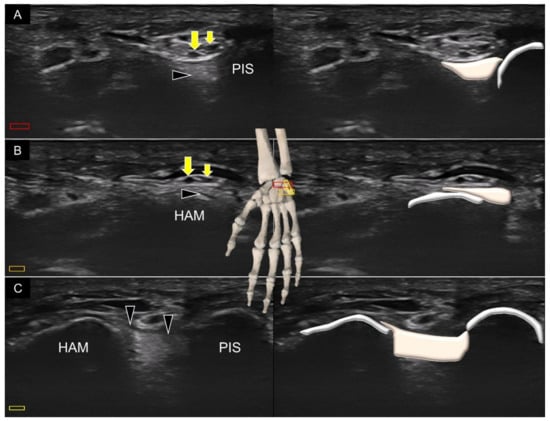

4. Sonoanatomy of Volar Intrinsic Carpal Ligaments